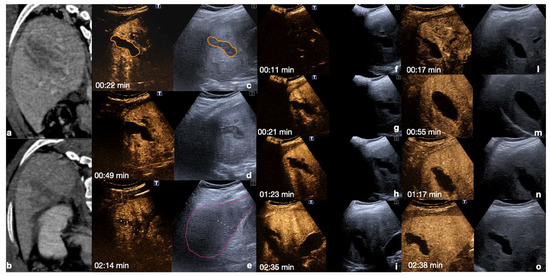

Kidney: the cortex enhances quickly and intensely after the injection, while the pyramids enhance from the periphery to the center in approximately 30 s [13,26]. The optimal time window for renal parenchymal injury assessment is up to 2.5 min following injection, as this is when maximum enhancement of the kidney can be observed [27,30] (Figure 4).

Figure 4.

CEUS findings in a normal kidney (a–f). Note the progressive physiological enhancement of the cortex and the medulla. Adopted from ref. [30], 2021, Iacobellis, F.; et al.

Liver: the arterial phase starts between 10–40 s after the injection. The hepatic and portal phases begin between 40–120 s after the injection, while the sinusoidal phase begins between 120–300 s after. Due to the dual vascular supply in the liver, a homogeneous parenchymal enhancement is shown that is adequate for the detection of organ injury (Figure 5) [13,26,30].

Figure 5.

CEUS findings in a normal liver (a–f). Note the progressive physiological enhancement of the liver in the different phases. Adopted from ref. [30], 2021, Iacobellis, F.; et al.

Spleen: the arterial phase starts 12–20 s after the injection. This phase shows irregular enhancement, similar to what is seen during MDCT, making it difficult to define any parenchymal injury. The venous phase starts 40–60 s after the injection. This phase provides adequate organ injury detection as the healthy parenchyma appears with a homogeneous enhancement for 5–7 min (Figure 7) [13,26,30].

Figure 7.

CEUS findings in a normal spleen (a–d). Note the progressive physiological enhancement after contrast medium injection. Adopted from ref. [30], 2021, Iacobellis, F.; et al.